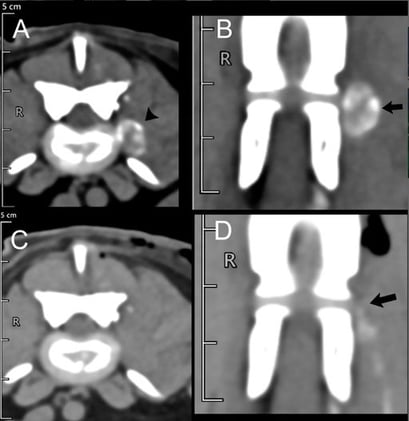

Oncology

Plos One 2025